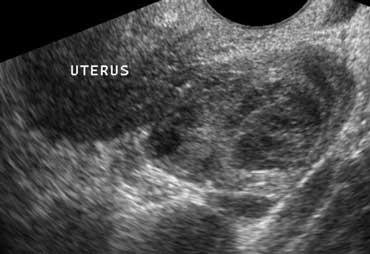

Lâm sàng nghi viêm ruột thừa. Siêu âm chỉ phát hiện một lượng nhỏ dịch cổ trướng. Chọc dò chẩn đoán (mũi tên chỉ đầu kim) cho thấy dịch máu. Ở phụ nữ, phát hiện này rất nghi ngờ thai ngoài tử cung (EUG).

Cổ trướng

Người tình nguyện khỏe mạnh không có lượng dịch tự do trong ổ phúc mạc có thể phát hiện được, ngoại trừ một lượng nhỏ dịch tình cờ ở túi cùng Douglas ở phụ nữ trong độ tuổi sinh sản.

Sự hiện diện của cổ trướng là dấu hiệu không đặc hiệu của bệnh lý ổ bụng, cho thấy ‘có điều gì đó bất thường’.

Có thể cân nhắc thực hiện chọc dò dịch cổ trướng dưới hướng dẫn siêu âm để xác định bản chất dịch: dịch phản ứng vô khuẩn, mủ, máu, nước tiểu hay dịch mật.